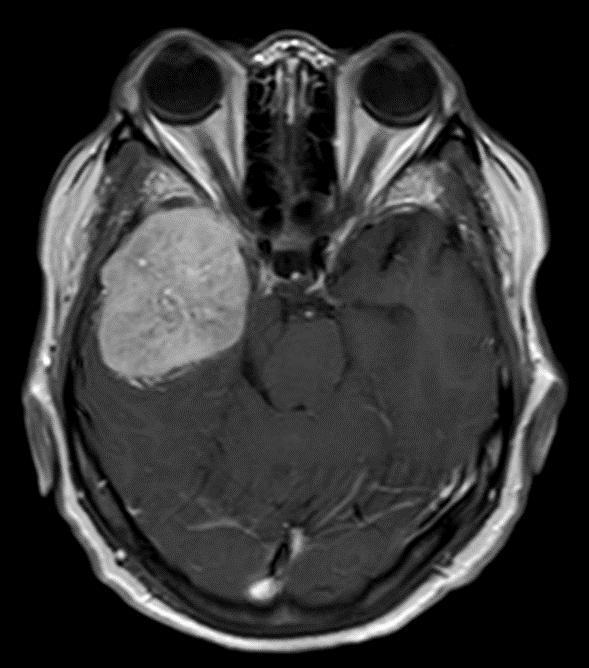

Рецидив менингиомы

Рецидив менингиомы 138 фото